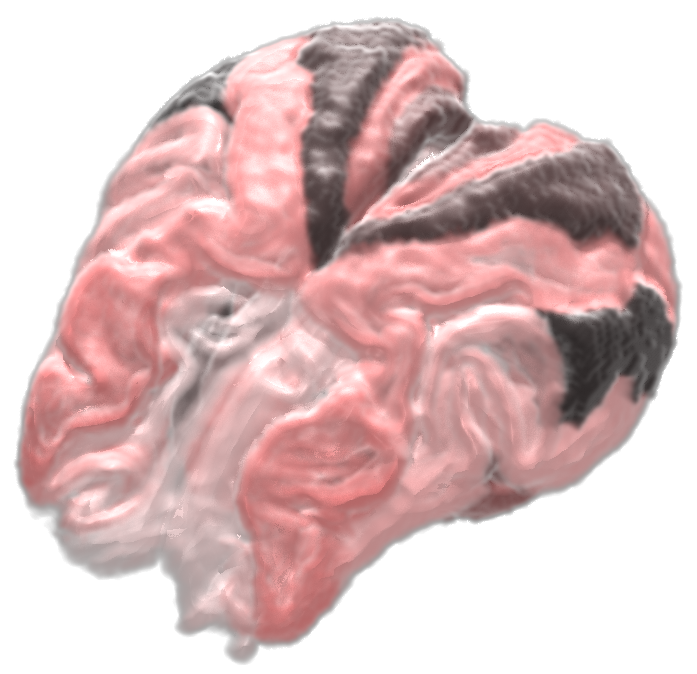

We proudly present atlases, templates, probabalistic tissue maps from sheep and dog to enable quantitative analysis of MRI datasets. The data were tested appropriately with SPM(8/12), but may work also with other software such as FSL.